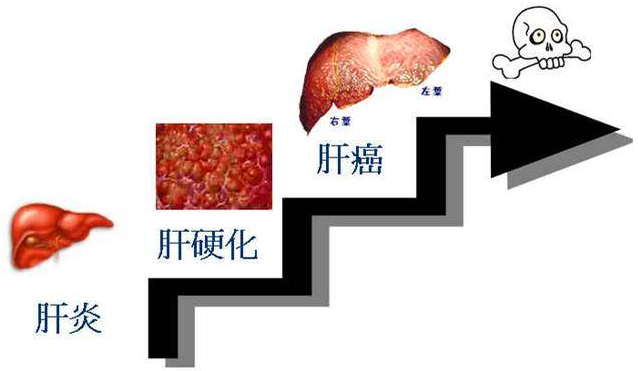

二、 乙肝没有控制好,当心引发肝硬化

「肝硬化、肝癌的出现大多都是由于肝炎时期没有得到有效控制」。

乙肝病毒会不断侵犯体内肝细胞,导致肝细胞损伤,肝细胞长期受损,肝脏结节改变,肝脏功能受到影响。

如果肝细胞长期反复受损,在修复过程中就会形成疤痕,疤痕越来越多,肝小叶结构完整性会被破坏,,形成假小叶,导致肝硬化,肝硬化结节是肝癌早期病变。